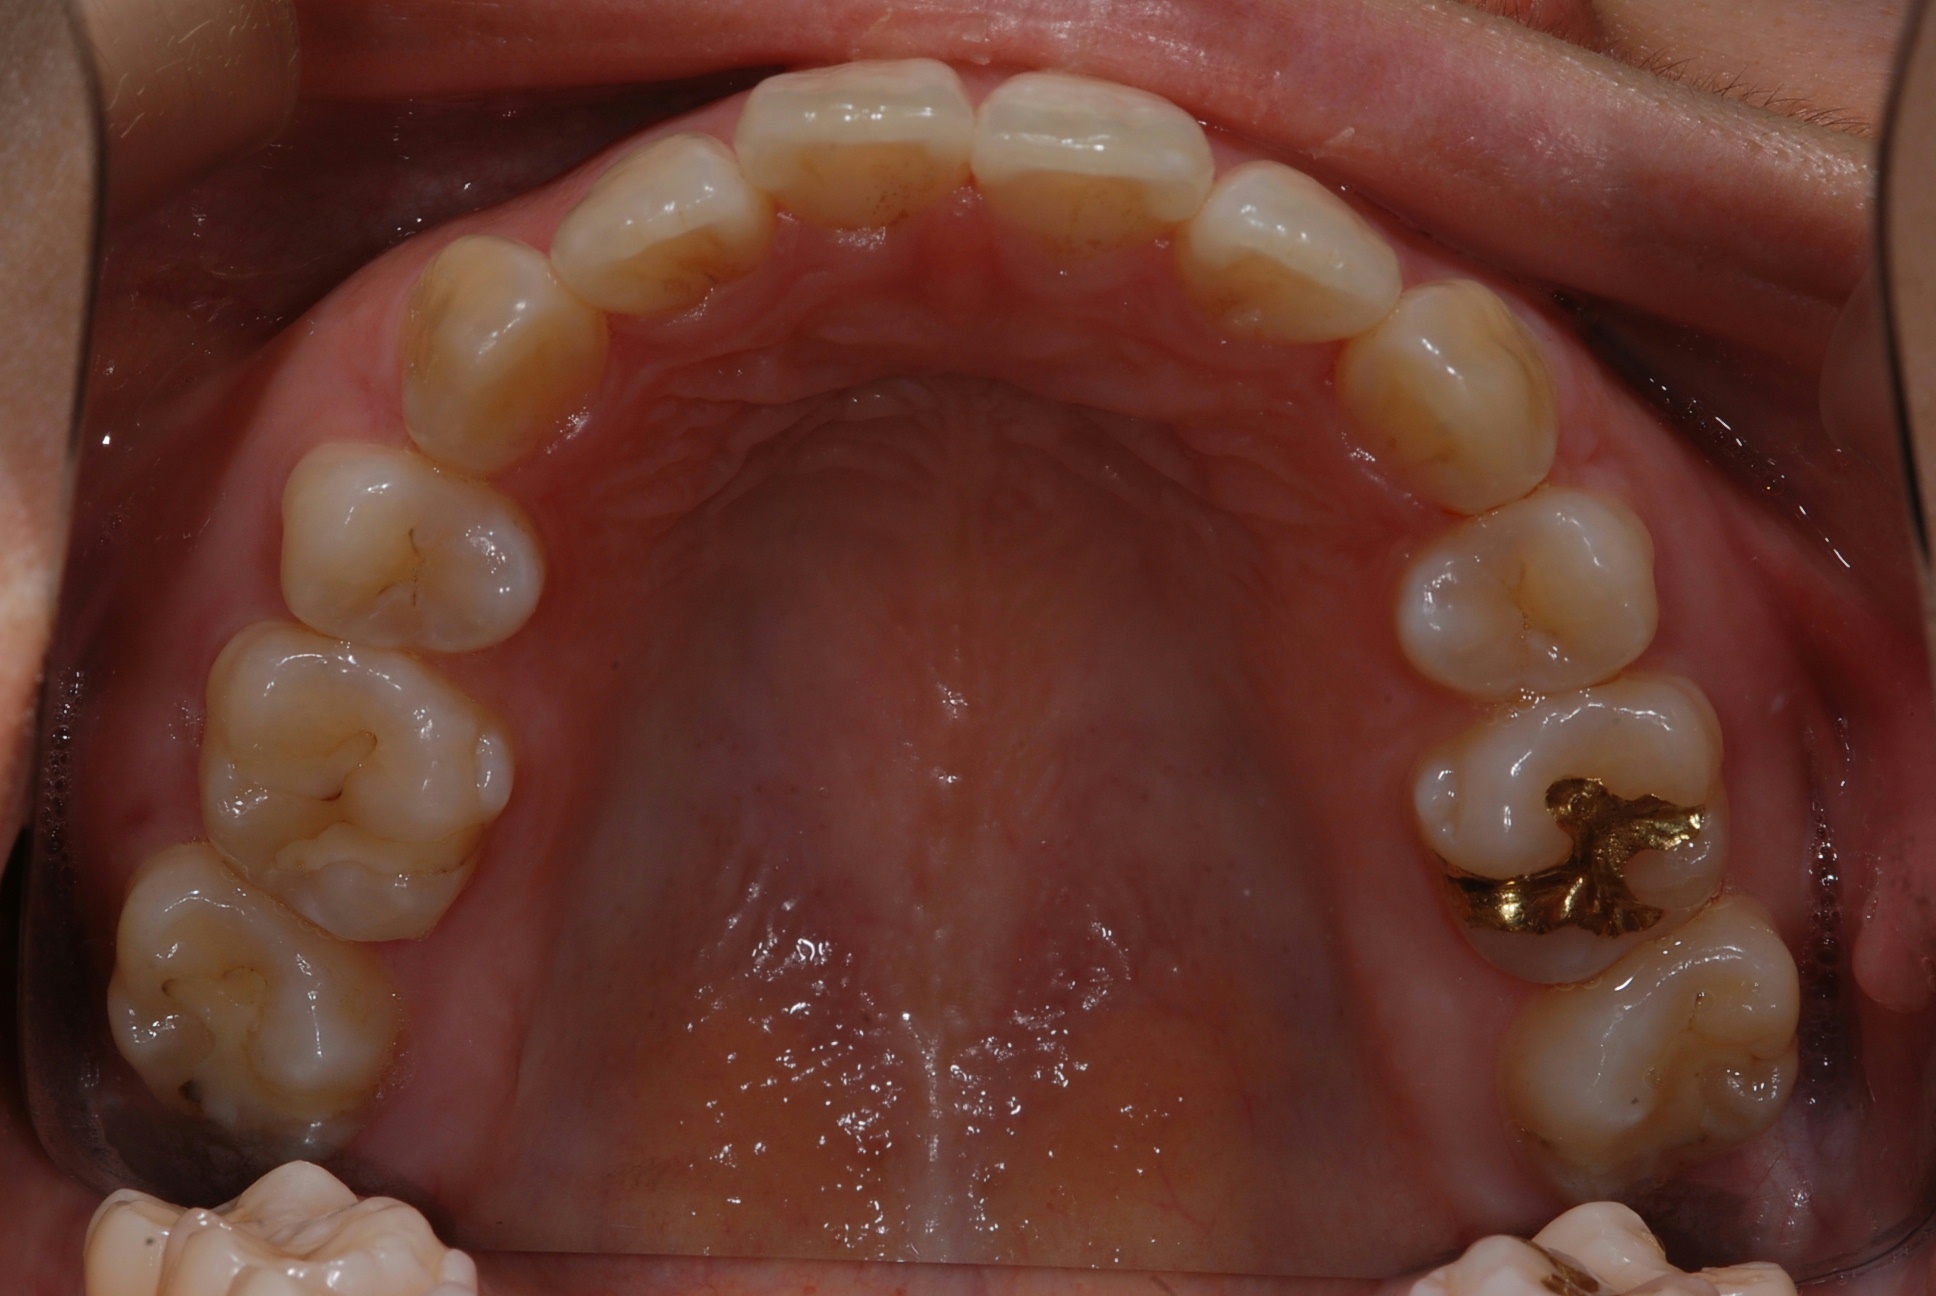

치료 전 사진입니다.